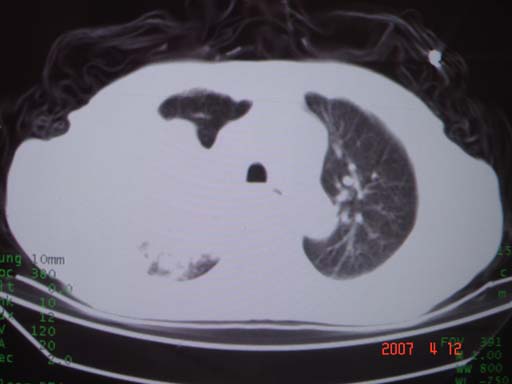

帮我 看看。男77岁咳嗽咯血2月发热2周!病人一般情况可 口痰为鲜红,有点象洗肉水(我看见他吐的痰了)

考虑右肺新生物伴右中上肺阻塞性肺炎及含气不良,右侧胸腔积液。建议痰与纤支镜检查

考虑右侧中央型肺癌伴中上肺阻塞性肺炎、不张,胸腔积液。,建议支纤镜检查。

病灶局限在右肺中上叶,呈大片状实变影,内见空气支气管征,支气管分支较柔软,纵隔内未见肿大淋巴结.支持:感染性病变_1 大叶性肺炎.2 干酪性肺炎.

优先考虑右上肺干酪性肺炎并同侧中叶播散、胸腔积液。分析:右膈肌未见升高、纵隔未见明显右移,胸部各组淋巴结未见可疑肿大,中叶可见支气管铸形,肺野、肺门未见可确定肿块。

年龄偏大,应考虑右肺中央型肺癌并阻塞性肺炎 阻塞性肺不张,胸腔积液

考虑右侧中心型肺癌伴中叶肺不张,右侧 胸腔积液

右肺上叶中心型肺癌并上叶阻塞性肺炎,中叶炎症,右侧胸腔积液

右肺上叶后段支气管中断,首先考虑中央型肺癌并右肺不张及纵隔淋巴结转移,右侧胸腔积液。

有点象洗肉水的痰,其来源应当是实变引起的血细胞渗出导致,可见支气管气象,实变区有虫蚀状空洞,有明显胸腔积液,未见明显肺门区肿块影,考虑继发型肺结核,干酪性肺炎

右肺上叶实变,实变范围如此之大,如果用肺癌解释的化,应该是比较大的支气管开口发生完全阻塞,但观察上叶前后段支气管还是比较通畅,所以应考虑感染性病变,大叶性肺炎可能,建议抗炎治疗后复查。

考虑右中上叶大叶性肺炎,右侧胸水。抗炎治疗后复查。